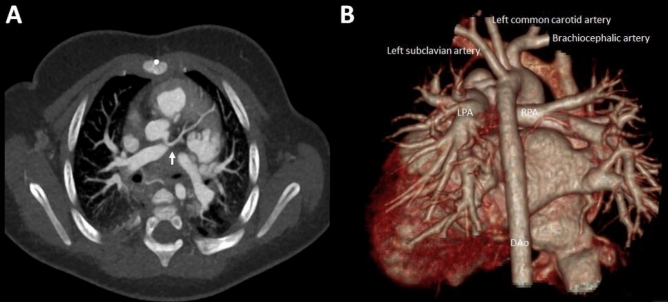

Figure 4.

Pulmonary vessel anatomy in an 8-month-old female infant with a tetralogy of Fallot demonstrating good delineation of the left anterior descending coronary artery (A; arrow). (B) Dorsal view of a 3-D reconstruction of the heart and the great vessels and pulmonary veins. LPA: Left pulmonary artery. RPA: Right pulmonary artery.